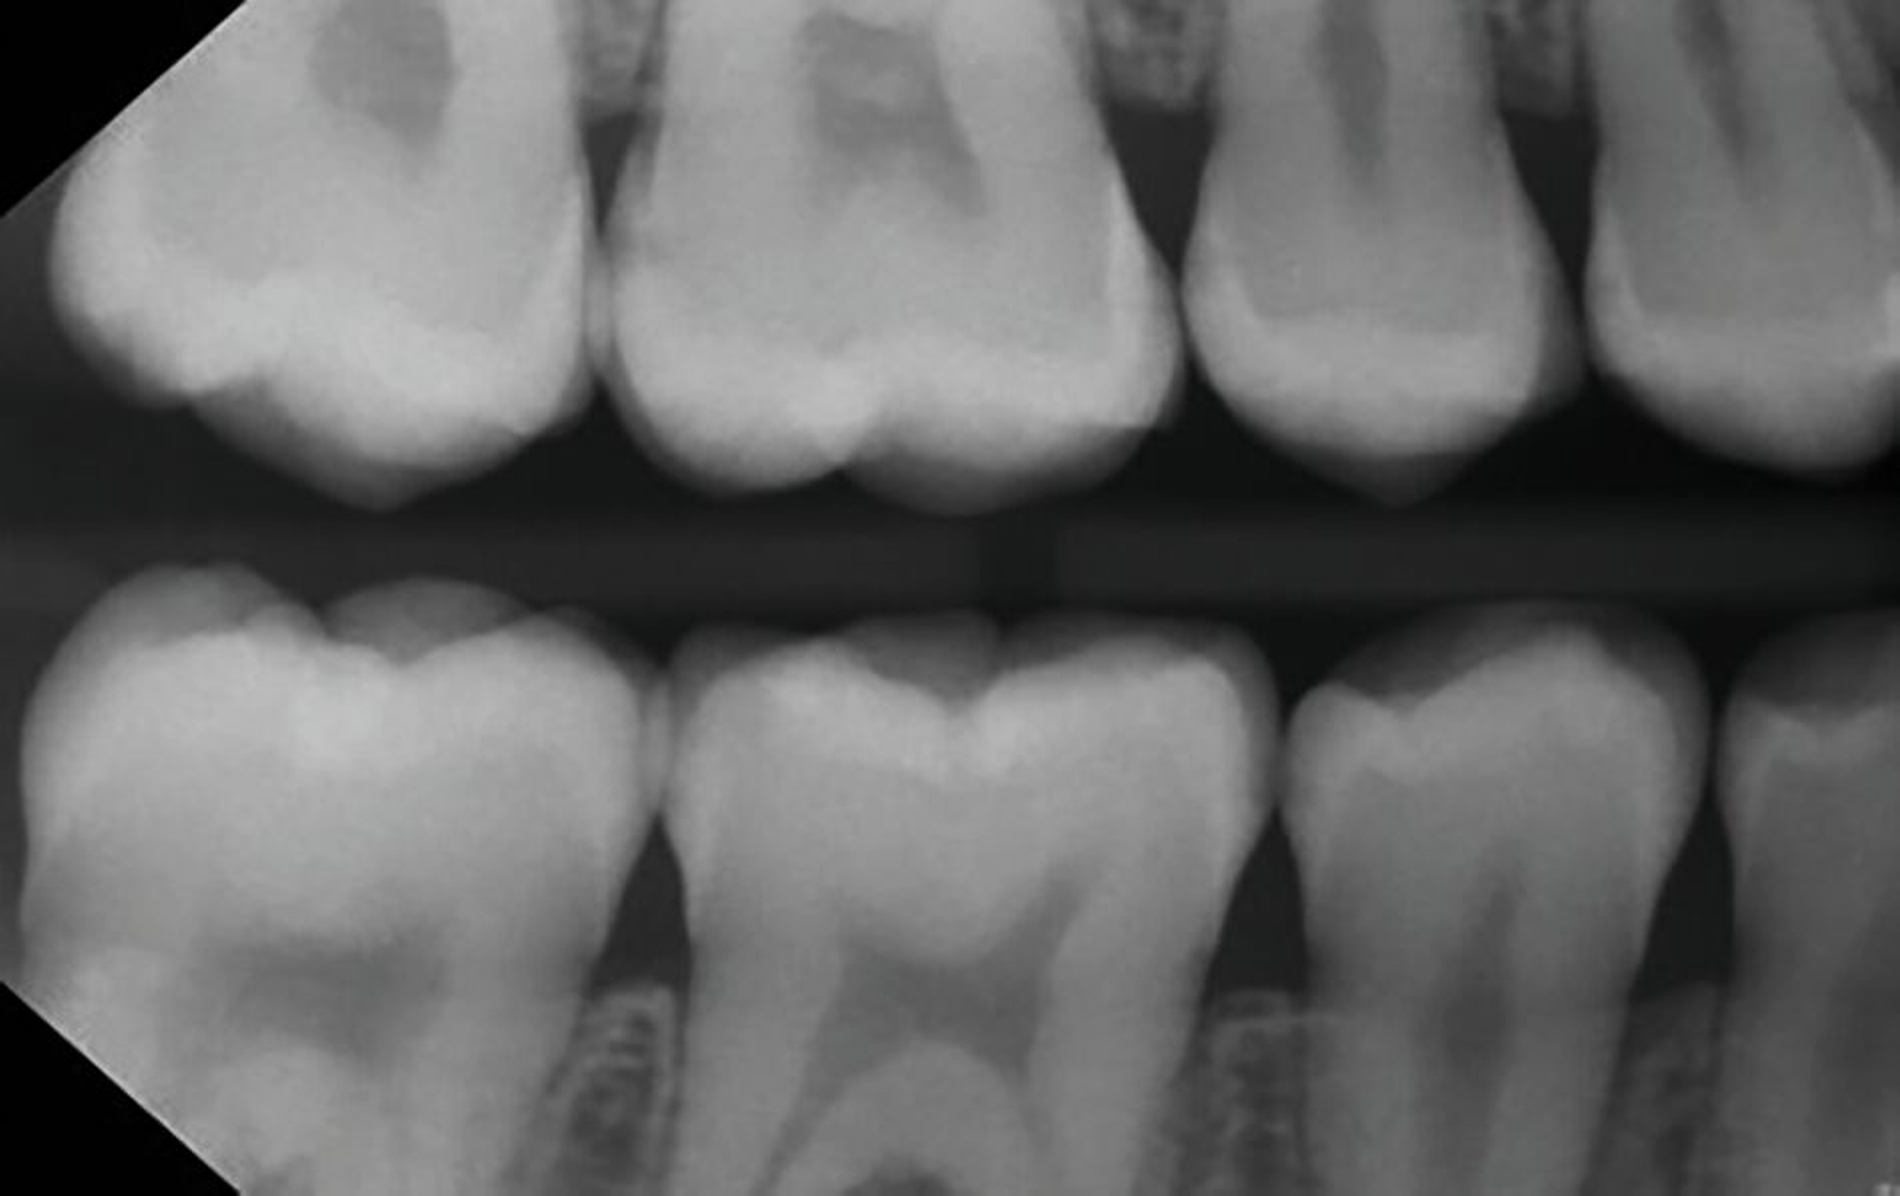

Der verkürzt dargestellte Patientenfall zeigt dieses minimalinvasive, innovative und kostengünstige Behandlungskonzept [Ahmed et al., 2023]. Im Kern werden dazu nach vorheriger Diagnostik orthodontische Separiergummis in die Zahnzwischenräume eingesetzt und für circa ein bis zwei Stunden in situ belassen. Direkt nach der Entfernung der Gummis erfolgt eine zügige, direkte klinische Untersuchung der Approximalkaries und eine Applikation von SDF zur Kariesinaktivierung mittels Microbrush.

Der Patientenfall belegt röntgenologisch die hohe Kariesaktivität vor der Behandlung, sowie die deutlich reduzierte Kariesaktivität nach der einmaligen SDF-Applikation in der oben genannten Technik nach knapp eineinhalb Jahren anhand von Bissflügelaufnahmen (Abbildungen 8a bis 8g). Eine retrospektive Pilot-Untersuchung an der Kinderzahnheilkunde in Greifswald gibt deutliche Hinweise auf die Wirksamkeit dieser Technik. Die Ergebnisse wurden beim diesjährigen Weltkarieskongress vorgestellt und diese Studie wurde ebenfalls von ORCA prämiert. Die Ergebnisse dieses Pilotprojekts zeigen für gut 90 Prozent der behandelten E1/E2/D1-Läsionen über einem Zeitraum von 15 Monaten keine weitere Progression in den Bissflügelaufnahmen [Ahmed et al., 2024].